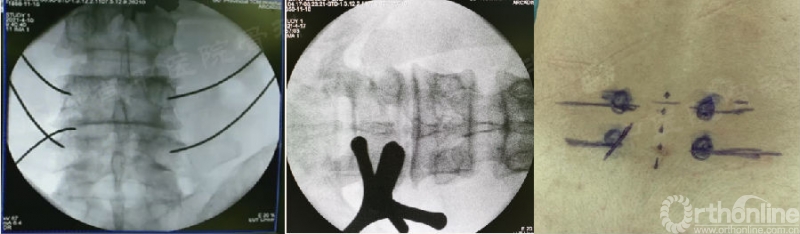

1. 切口

切口形状:3竖一斜/横,3横一斜,4横等;

减压OR打钉:可先后。